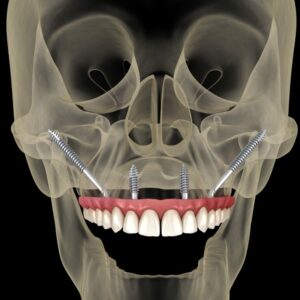

Reviewed by Richard Dawson, DMD — General & Implant Dentist, ICOI Fellow, Smile Science Dental Spa What Are Zygomatic Implants? Zygomatic implants are extra-long titanium implants anchored in the zygomatic bone (the cheekbone) rather than the jaw. While conventional dental implants are 8 to 16 mm long and placed entirely within the alveolar bone of […]

Read Zygoma Implants: A Definitive Guide